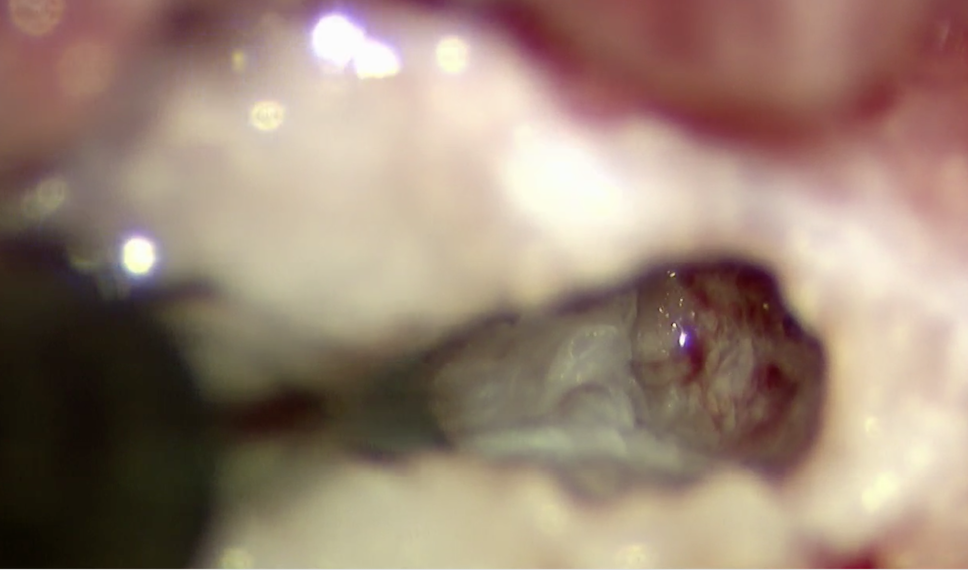

今回の症例では骨の幅が9mmであり、削る幅の最大径が3mmでした。それ以上の幅で削ると不安定性が出て合併症のリスクが高くなります。3mmの幅の内部での操作となるため、肉眼での操作は困難であり、顕微鏡操作が有用となります。以下は顕微鏡下での術野の視野になります。

骨を少しずつ掘っていきます。

穴が深くなっています。

内部の白いものが椎間板物質になります。